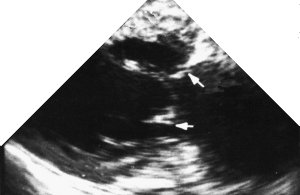

3. Two chamber view + LAA

4. The left atrial appendage is important. Here you can see that it often has coarse trabeculation, and in addition the junction of the left upper pulmonary vein and left atrium close to the LAA can give a mass-like effect.